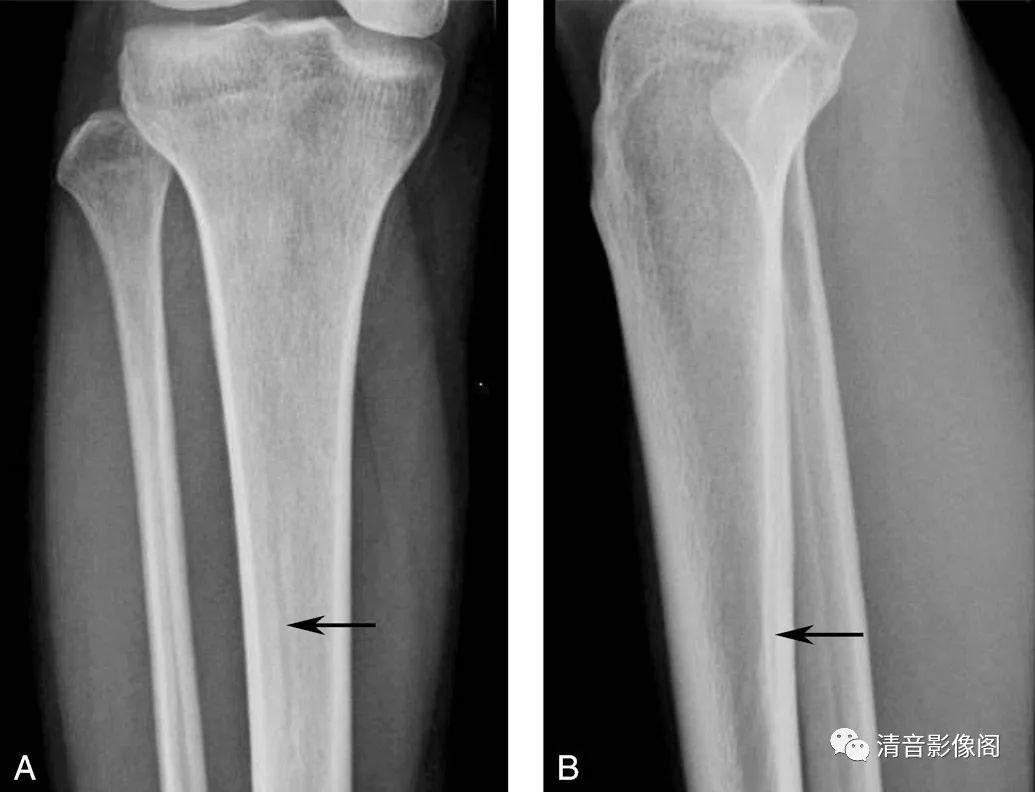

骨滋养管

A. 正位上胫骨上段可见纵行线样透亮影(箭),透亮线边缘有硬化缘,为滋养血管的投影,非裂隙性骨折;B. 侧位可见线样影从皮质的后上向前下走行,至骨髓内消失,不会穿越骨干(箭)。